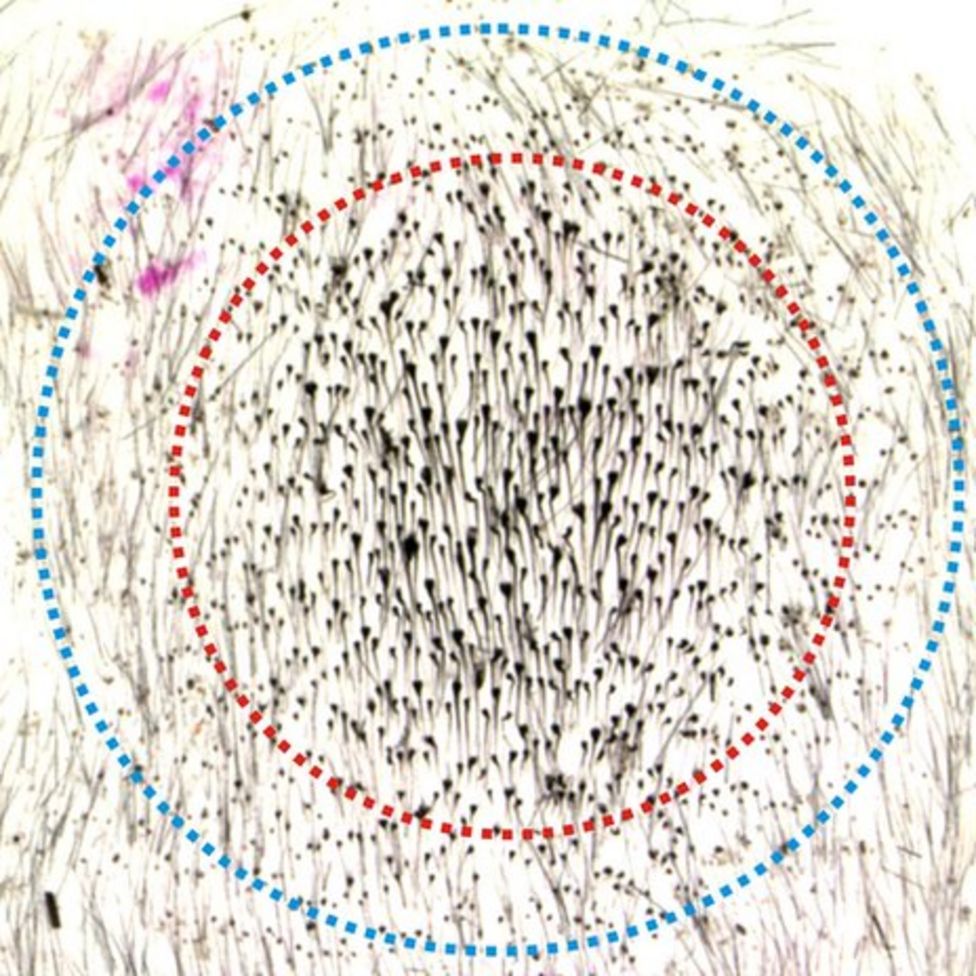

Plucking Hairs can Make More Grow BBC News

https://ichef.bbci.co.uk/news/976/mcs/media/images/82203000/jpg/_82203640_89363.jpg